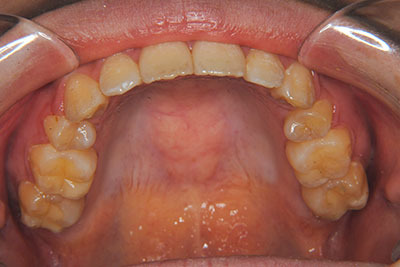

おとなの方でも矯正治療をあきらめないでください!

子供の頃に矯正治療を行う方が治療期間が短く済むというのは、確かですが、矯正治療は患者様の意識も重要です。

いくら歯が動き易くとも、本人がやる気でなければ効果は出ませんし、むし歯発生のリスクも高まります。おとなの方は顎の成長が終わっているため、治療の計画が立てやすいとも言えます。「もう大人だから…」とあきらめず、一度ご相談ください。